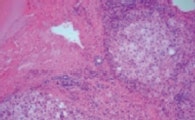

How does the Olympus True Color LED perform on real-world samples? To test this, the performance of the True Color LED was visually evaluated by direct comparison against other commercially available LED light sources on common histological stains: Hematoxylin and Eosin (H&E) and Azan Trichrome (figure 8).

Figure 8: Comparing LED Light Sources

Both in H&E-stained (a-d) and in Azan-stained tissue sections (e-h) True Color LED illumination shows no discernable color shifts compared to halogen lamp whereas other commercially available LED sources show distinctive yellow shifts (c and g) or blue shifts (d and h).